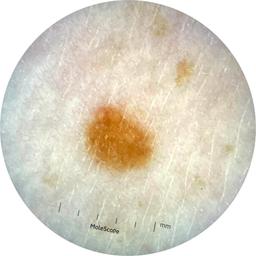

ISIC_9785574

Information

2003 x 2003

Attribute to

MEL-SELF Trial, https://www.sydney.edu.au/medicine-health/our-research/research-centres/melself-project.html

License

Clinical

Field Value

acquisition_day 148

age_approx 45

anatom_site_1 Head and neck

anatom_site_general head/neck

concomitant_biopsy False

diagnosis_1 Benign

diagnosis_confirm_type single image expert consensus

family_hx_mm True

image_manipulation instrument only

image_type dermoscopic

lesion_id IL_0236417

patient_id IP_8456088

personal_hx_mm True

sex female